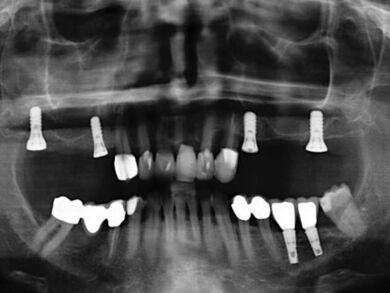

Patientenfall: Brückenversorgung auf jeweils zwei Implantaten